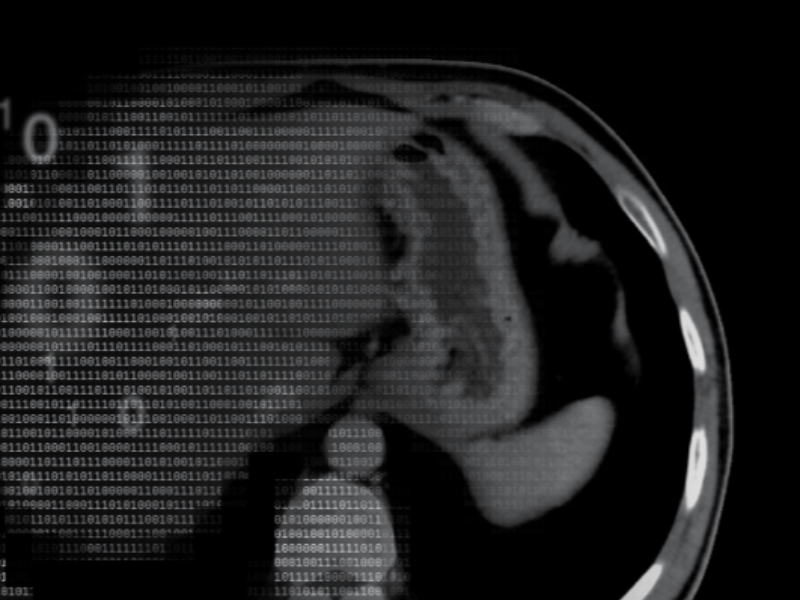

Bariatric abdomen/pelvis exam revels hernia